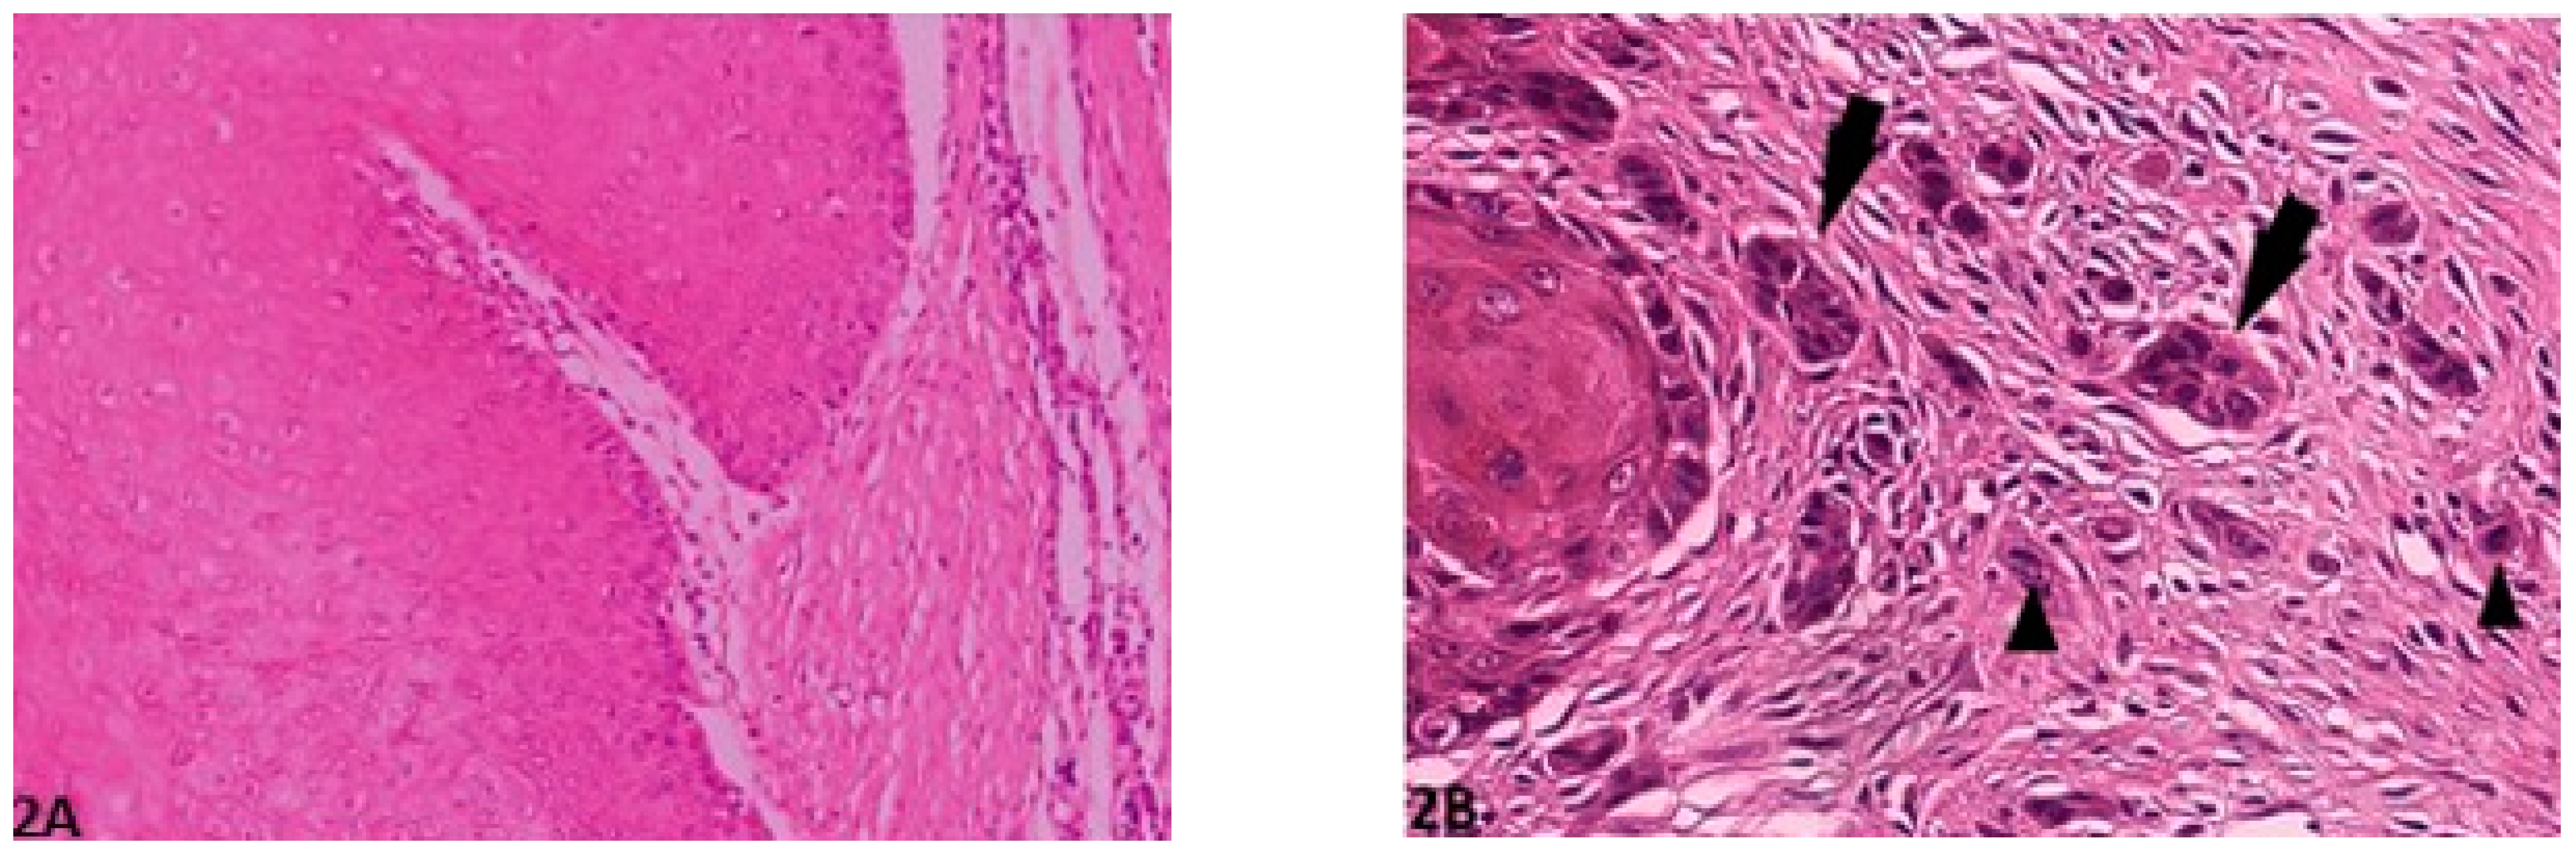

2.2.1. Invasive front Grading System (IFGS)

2.2.2. Tumor Cell Budding Grading System (TCBGS)

| Degree of keratinization | Highly keratinized (>50% cells) | Moderately keratinized (20–50% of cells) | Minimal keratinization (5–20% of cells) | No keratinization (0–5% of cells) |

| Pattern of invasion (bone or dermis) | Pushing, well-differentiated, infiltrating borders | Infiltrating, solid cords, bands and/or strands | Small groups/cords of infiltrating cells (n > 15) | Widespread cellular dissociation in small groups and/or in single cells (n < 15) |

| Host response | Marked | Moderate | Slight | None |

| Nuclear pleomorphism | Mild (<25% anaplasia) | Moderate (25–50% anaplasia) | Marked (50–75% anaplasia) | Extreme (75–100% anaplasia) |

| Mitosis HPF (40×) | 0–1 | 2–3 | 4–5 | >5 |